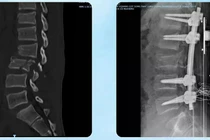

5 chuyên khoa và 10 giờ phẫu thuật cho ca bệnh “chưa từng có tiền lệ” đã điều trị thành công cho bệnh nhân ung thư hốc mũi giai đoạn muộn.

Nhờ sự phối hợp chặt chẽ giữa các khoa chuyên môn cùng việc áp dụng kỹ thuật cao, bệnh nhân vượt qua giai đoạn nguy kịch.